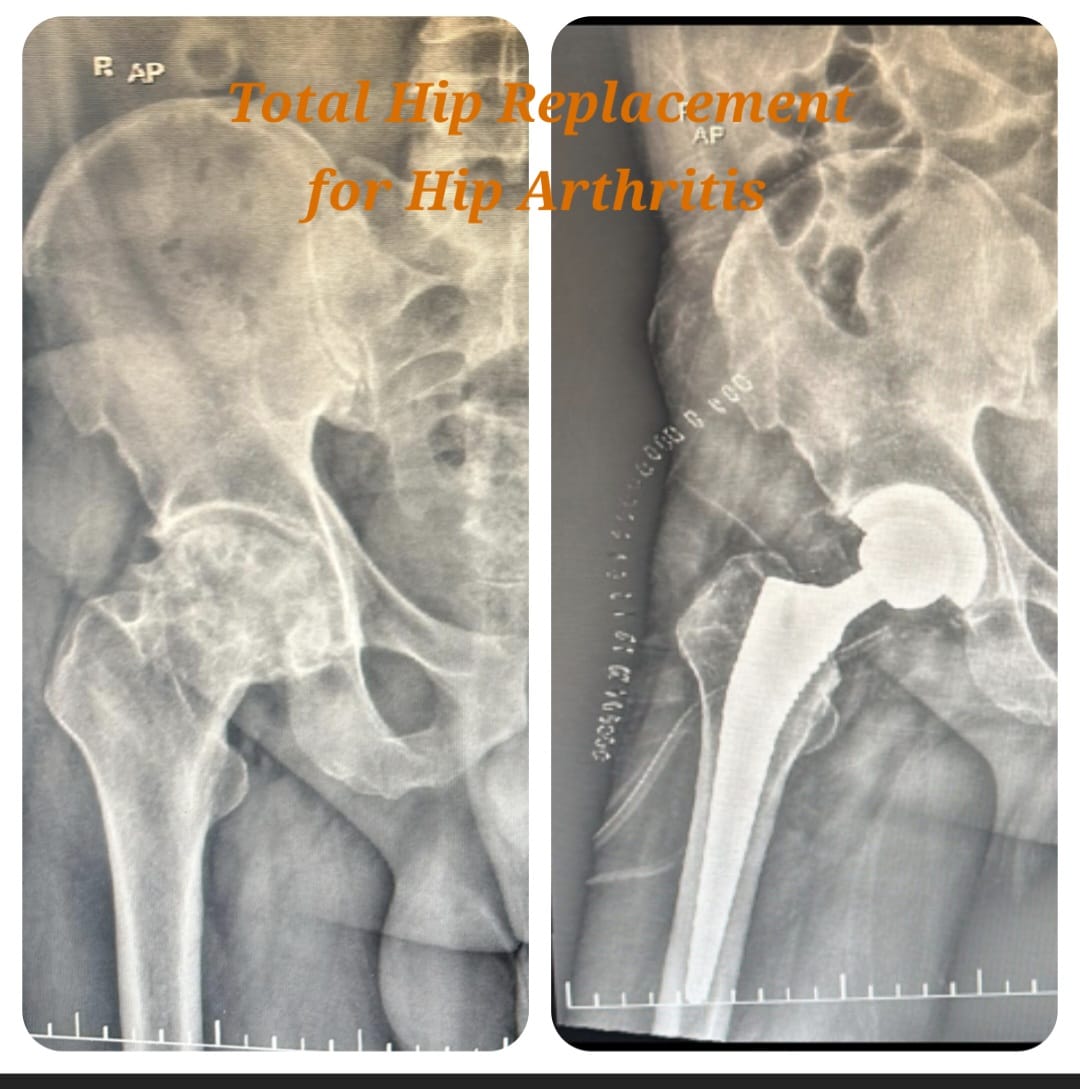

Primary total hip replacement is a definitive surgical procedure performed to relieve severe hip pain and restore joint mobility in patients suffering from advanced hip arthritis, fractures, avascular necrosis, or extensive joint damage. The procedure involves replacing the damaged hip joint surfaces with high-quality artificial implants designed to provide smooth, stable, and pain-free movement.

This surgery is recommended when conservative treatments such as medications, injections, physiotherapy, and lifestyle modifications fail to provide lasting relief. Careful preoperative planning and modern surgical techniques ensure accurate implant positioning, optimal joint alignment, and long-term durability.